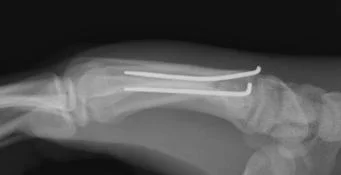

Mallet Finger

Avulsion injury of extensor tendons insertion to distal phalanx

Mechanism of injury

- Sudden forceful flexion (e.g. ball hits tip of finger)

Clinical picture

- Flexed distal IP joint

- Loss of active extension of DIP joint

Treatment

- Mallet finger splint

- Internal fixation if avulsed bone is large